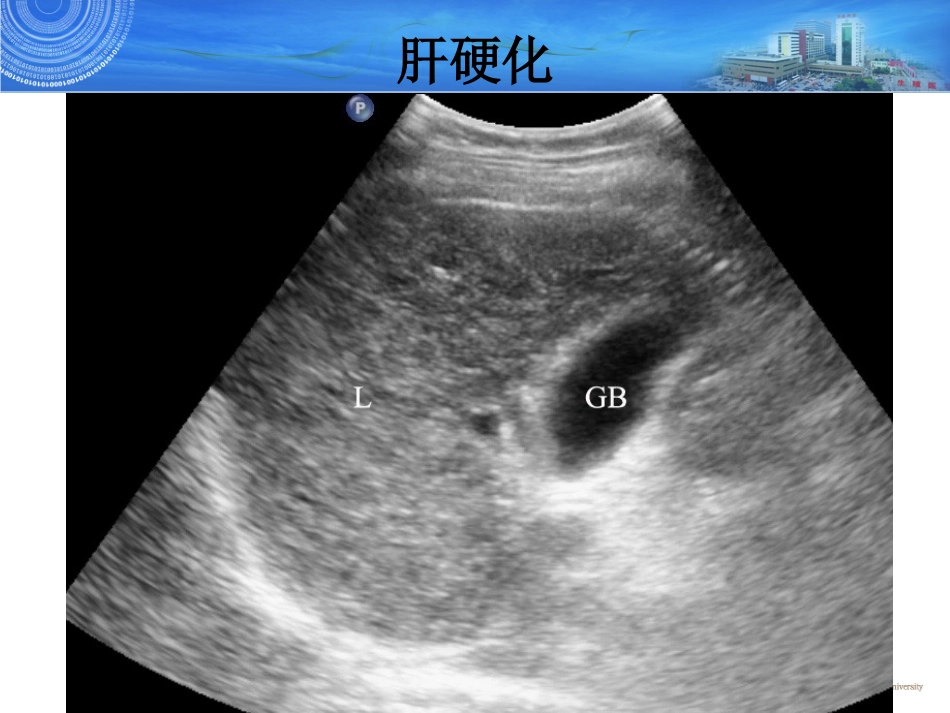

腹部常见疾病超声腹部常见疾病超声诊断诊断侯曼曼疾病种类1.肝硬化2.急性胆囊炎3.胆囊结石4.肾结石肝硬化正常肝实质回声呈细小中等点状回声,分布均匀,有时可见稀疏、散在的略强点状及短小线状回声。正常肝超声表现•一种常见的慢性肝病,可由一种或多种原因引起肝脏慢性损害,肝脏呈进行性、弥漫性、纤维性病变。具体表现为肝细胞弥漫性变性坏死,继而出现纤维组织增生和肝细胞结节状再生。本病早期无明显症状,后期则出现一系列不同程度的门静脉高压和肝功能障碍,直至出现上消化道出血、肝性脑病等并发症。肝硬化•灰阶超声:典型肝硬化时,左右叶均缩小或左叶代偿性增大。肝包膜呈锯齿状。肝区回声增粗增强,部分呈颗粒状、结节状,可表现为低回声或高回声结节,多在0.5-2.0cm。肝内血管粗细不均或纹理紊乱,肝静脉常变细,门静脉可增宽,肝动脉可代偿性增宽。脾大、腹水、胆囊壁增厚。•彩色多普勒:门静脉扩张(>1.3~1.5cm),脉冲多普勒示门脉血流速度降低,部分呈双向甚至反向的离肝血流,个别门脉内可有血栓形成;肝动脉较正常者易显示或增宽,脉冲多普勒显示其流速增高,且RI亦增高;肝静脉变细、颜色变暗,脉冲多普勒示其流速减低,呈类似门静脉血流。同时,彩色多普勒还可显示脐静脉重开,并可见该彩色血流与门脉矢状段囊部血流相通,腹壁静脉曲张,食管胃底静脉曲张,脾静脉增宽等肝硬化灰阶超声,肝硬化,显示肝实质回声增强增粗,分布不均。L:肝脏GB:胆囊肝硬化图1图2灰阶超声,显示的门静脉增宽达14mm(图1),肝实质内变细、浅淡的肝静脉(图2,箭头所示)PV:门静脉IVC:下腔静脉L:肝脏灰阶超声,肝硬化门脉高压,显示胰腺处脾静脉增宽,达20mm(图1,箭头所示)。彩色多普勒,显示增宽的脾静脉为彩色血流信号所填充(图2,箭头所示)肝硬化胆囊解剖•胆囊位于肝右叶脏面的胆囊窝内,多呈梨形。•胆囊大小:长径5~8cm,横径3~4cm,胆囊壁厚2~3mm。•胆囊分为底、体、颈三部分。胆囊的解剖概要正常胆囊声像图GB:胆囊;CBD:胆总管;PV:门静脉;LIVER:肝脏正常胆囊超声表现•好发于多产、肥胖的中年女性。•典型胆囊结石声像图特点:1.无回声胆囊内出现点状或团状强回声。2.强回声后方伴声影。3.随体位改变沿重力方向移动。胆囊结石声像图表现为强回声团后方伴有声影GB:胆囊;ST:结石;LIVER:肝脏胆囊结石胆囊泥沙样结石1.主要成分为胆色素。2.声像图表现•胆囊后壁分布的厚薄不一的强回声带,后方伴较宽的声影。胆囊结石泥沙样结石声像图表现:胆囊后壁强回声带后方伴声影;GB:胆囊;箭头示泥沙样结石胆囊泥沙样结石急性胆囊炎1.大多数由结石嵌顿引起。2.主要的临床特征是右上腹持续性疼痛并阵发性加剧、发热、右上腹压痛,超声Murphy征阳性。3.声像图主要表现为胆囊肿大、胆囊壁增厚、胆汁浑浊,多合并胆囊结石。胆囊颈部结石合并急性胆囊炎急性胆囊炎•急性化脓性胆囊炎:胆囊肿大,胆囊壁增厚,胆囊内透声差,充满稀疏或密集的细小或粗大光点。急性胆囊炎肾脏解剖正常肾脏超声表现肾结石肾结石超声表现1.肾窦内出现点状、团块状强回声,后伴声影。一般含钙结石超声穿透性差,声影显著,、多非含钙结石鹿角状结石穿透性较好,声影欠显著。可单发发,鹿角状结石有不规则分支,或呈数个分散的强回声,实时超声局部侧动扫查可见这些强回声相互连接在一起。2.多数结石CDFI检查可见有特征性的快闪伪像(结石及其声影部位出现彩色镶嵌),出现率约80%左右。3.肾结石继发肾积水,出现结石梗阻引起肾盂肾盏扩张表现。超声能发现0.3-0.5cm以上的肾结石,敏感性高达96%。肾窦内强回声团块,后伴声影,肾盂肾盏梗阻分离(肾积水)肾结石左肾盏多个强回声,强回声后伴声影,肾盏扩张积水肾结石鹿角样结石,肾窦区多个强回声,形态不规则,相互连接,后方伴声影肾结石肾结石快闪伪像